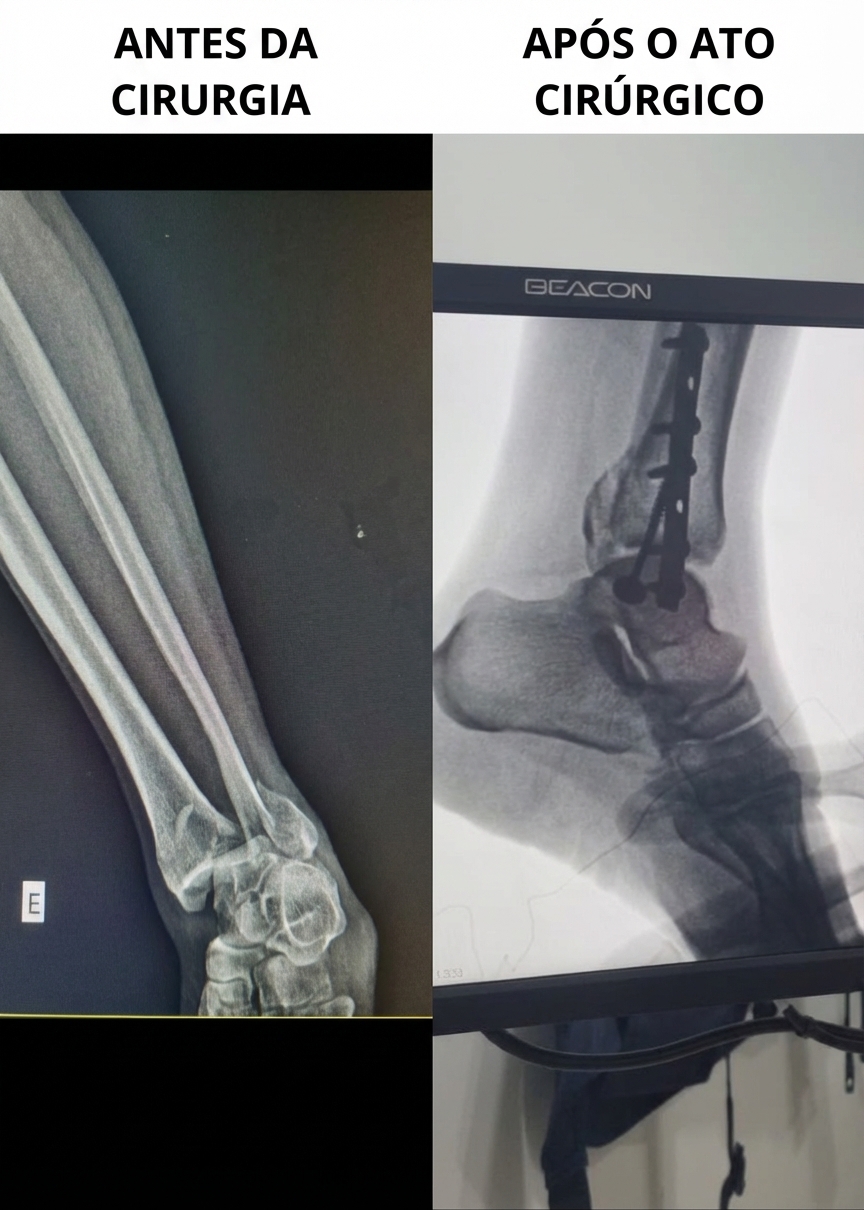

No dia 13/04/2026 às 8:00 deu entrada uma lesão grave que compromete a articulação, no Hospital Estadual do Oiapoque, o caso tratava-se de uma fratura trimaleolar no tornozelo. Segundo o Dr. Otávio Ferreira, Médico Ortopedista, Chefe do Setor responsável pelo procedimento, a redução manual não seria suficiente para estabilizar a articulação.

"A gente abordou a lateral, fez uma redução com placa e parafuso, e no maléolo medial usamos parafuso e arruela"

Explicou o especialista. A agilidade impressiona: da entrada no hospital até a mesa de cirurgia, passaram-se apenas 7 horas — um tempo de resposta que supera até mesmo os padrões do hospital na capital.

Antes e após Cirúrgia Ortopédica